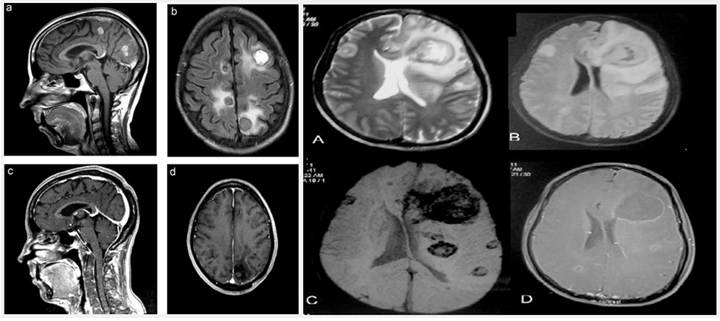

图片

注:溺水后尖端赛多孢引起的致命性的脑脓肿和脑室炎[7]

注:尖端赛多孢引起慢性肉芽肿炎(免疫功能正常患者)[8]

注:尖端赛多孢引起真菌性心内膜炎(心脏移植患者)[9]